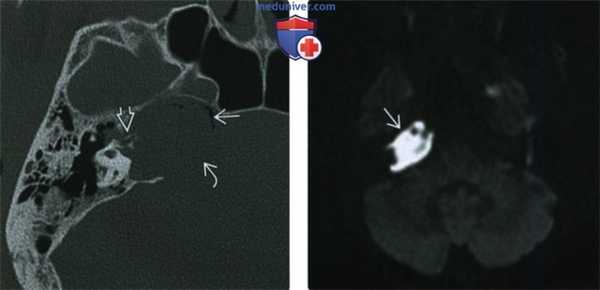

(Слева) При КТ в костном окне определяется распространенное образование с тотальной деструкцией передненаружного края. Образование распространяется в ВСК и приводит к эрозии слуховой капсулы. Кавернозный сегмент ВСА смещен кпереди.

(Справа) При аксиальной КТ височных костей (более каудальный срез) у этого же пациента визуализируется ХГ-ВП, сдавливающая костную часть евстахиевой трубы. Жидкость в сосцевидном отростке обусловлена обструкцией евстахиевой трубы.

(Слева) При аксиальной КТв костном окне в пневматизированной ВП слева визуализируется холестериновая гранулема в виде хорошо отграниченного экспансивного образования овоидной формы. Задняя стенка ВА истончена или отсутствует.

(Справа) При аксиальной МРТ Т1 у этого же пациента определяется гиперинтенсивный сигнал в левостороннем экспансивном образовании овоидной формы, сопоставимом с холестериновой гранулемой.

(Слева) При аксиальной КТ правой височной кости визуализируется врожденная холестеатома с ровными краями и интрамуральными включениями газа, приводящая к расширению вершины пирамиды. Холестеатома приводит к эрозии кост ного лабиринта внутреннего уха и дефекту кортикального слоя задне-медиальных отделов ВПВ.

(Справа) При аксиальной МРТ ДВИ у этого же пациента определяется гиперинтенсивный сигнал (рестрикция диффузии), характерный для врожденной холеаеатомы ВП.